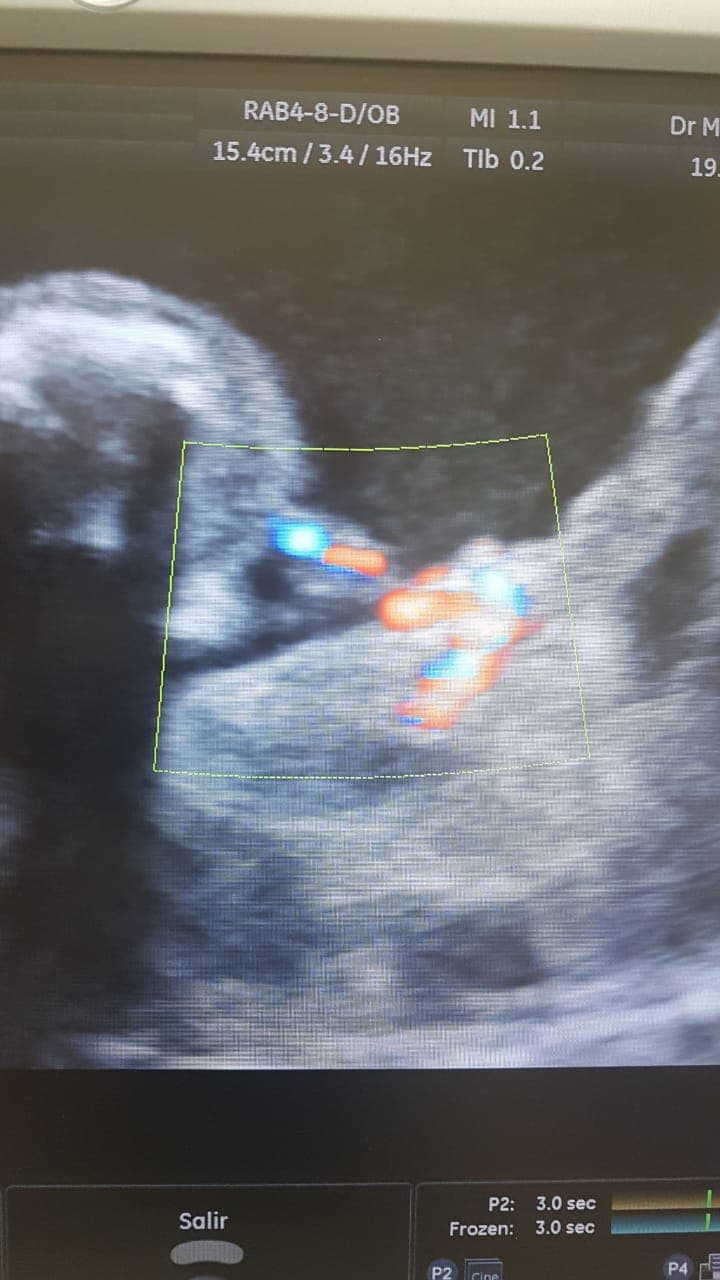

Cuando la mamá, de 33 años, fue revisada a unas cinco semanas del término del parto, el doctor que la revisaba había pensado que el feto (Itzmara) tenía un quiste.

Pero luego por medio de equipos de alta tecnología en la clínica La Merced de Barranquilla pudieron notar que se trataba de un 'bebecito' con cordón umbilical conectado a su gemela.

Parra Saavedra detalla que extraer al pequeño feto del cuerpo de Itzamara "fue complejo porque no sabían lo que iban a encontrar en el abdomen". Para buscar el sitio exacto en donde estaba pegado el feto, el equipo de especialistas primero tuvo que visualizar el interior con una ecografia intraoperatoria.